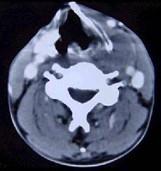

问题 男性,40岁,发现左侧颈部小包块,CT、MRI检查如图所示,请选择最可能的诊断()

选项 A.神经鞘瘤 B.神经纤维瘤 C.海绵状血管瘤 D.肿大淋巴结 E.副神经节瘤

答案 C